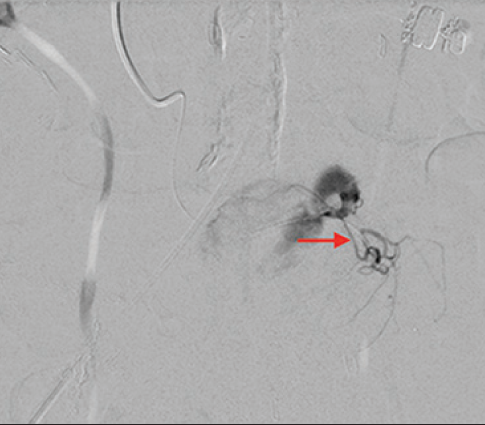

病例三 77岁女性复发性胃肠道出血,需要多次输血并入住ICU。(d)栓塞后无外渗。箭头指向栓塞部位。

激发试验药物剂量和结果![]() 、、 ![]() 本文是一篇发表在《Journal of Gastrointestinal Surgery》上的研究通讯文章,题目为“Provocative Mesenteric Angiography: Outcomes and Standardized Protocol for Management of Recurrent Lower Gastrointestinal Hemorrhage”。该研究旨在评估激发肠系膜血管造影(PMA)在复发性下消化道出血中的有效性和并发症,并探讨是否可以在多学科环境中建立一种技术操作规程。 研究方法研究团队回顾了其机构在过去12年(2008年至2020年)期间进行的下消化道出血肠系膜血管造影的数据,基于CPT代码75726筛选出符合条件的病例。进一步分析了其中的PMA病例,排除了医源性、手术性或创伤性原因引起的下消化道出血。挑衅性造影的诱导方案包括使用硝酸甘油扩张血管、肝素抗凝以及组织纤溶酶原激活剂(tPA)溶解血栓。 研究结果在12年的研究期间,共进行了36例PMA。其中16例(44%)为阳性结果,20例(56%)为阴性结果。阳性组和阴性组之间在患者人口统计学特征、既往下消化道出血史、先前住院次数、Charlson合并症指数评分或术前血红蛋白水平方面没有显著差异。所有阳性病例均接受了栓塞治疗,且无出血并发症,无再出血事件,也未出现缺血性肠病后遗症。尽管有两名患者(12.5%)在30天内因复发性出血再次入院,但这一比例显著低于在阴性研究中再出血的60%。 结论本研究是迄今为止最大的文献,表明PMA在适当选择的患者中能够成功诱发和治疗下消化道出血。此外,该程序是安全的,即使使用较高剂量的tPA,也没有发生出血或缺血性肠病并发症。研究机构采用了一种修改后的现有社会指南协议,将PMA纳入下消化道出血的管理流程。 其他信息文章还提到了一些相关的参考文献和被引用的文章,涉及早期与标准结肠镜检查、急性下消化道出血的门静脉造影预测因素和结果、隐匿性胃肠出血的挑衅性肠系膜血管造影更新等内容。这些文献提供了更多的背景信息和相关研究支持。 激发血管造影并发症 与“激发”试验直接相关的并发症